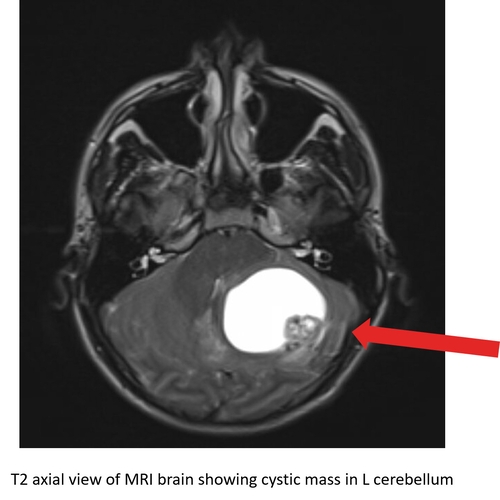

| Don't Worry, It's All In Your Head! - Page #3 | |||